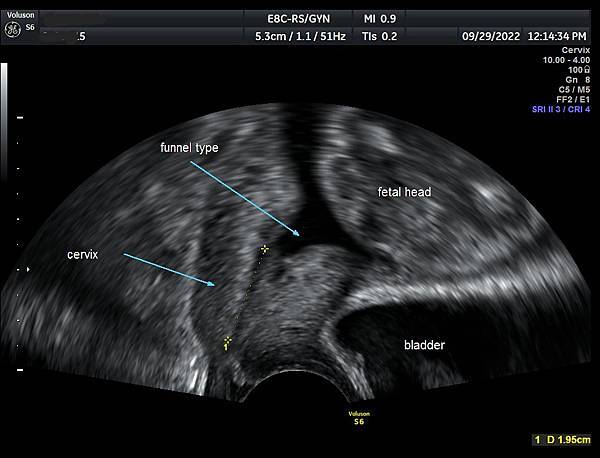

• 孕兒診所賴錫鉅醫師 385 子宮頸長度測量預防早產 - 5 漏斗型子宮頸產前診斷經驗分享

子宮頸長度測量預防早產 - 5

漏斗型子宮頸產前診斷經驗分享